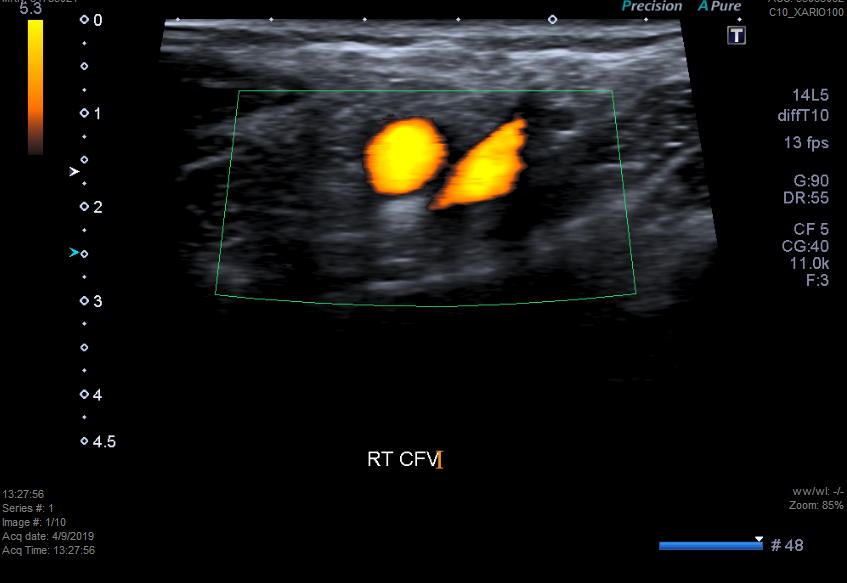

Other Investigations